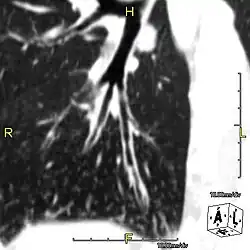

Oblique sagittal CT image showing lower lobe cylindrical bronchiectasis in the same patient